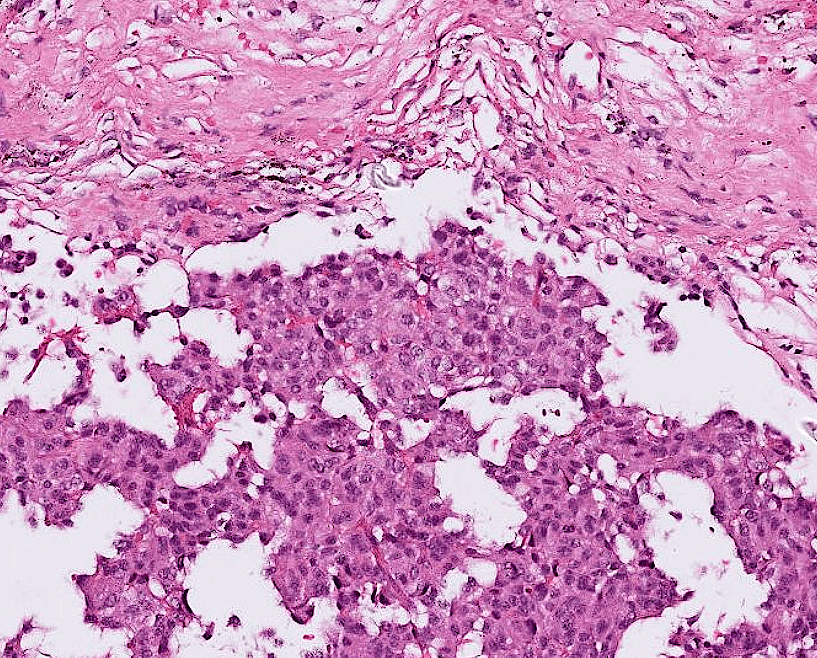

endometrial cancer